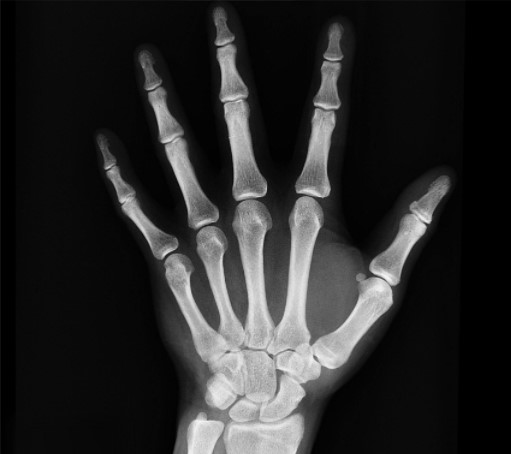

Cartilage lacks blood vessels, so it heals poorly. Over time, repetitive stress wears down this cushion, causing inflammation and bone spurs. Knees, hips, and hands are most vulnerable.